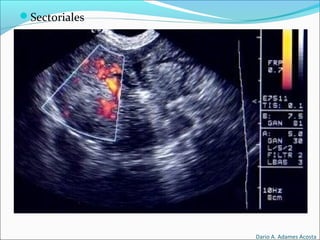

Tipos de Transductores

Sectoriales

Formato de imagen

triangular o en abanico

Base de inicio de la

emisión de los ecos

mínima.

Se usan en la exploración

cardiaca y abdominal ya

que permiten tener un

abordaje intercostal.

Al usarse para la

exploración de estructuras

más profundas su

frecuencia de trabajo suele

ser entre 3.5 y 5 MHz